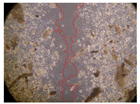

In the present study, the healing potential of 8 decoctions used in the preparation of ayahuasca was evaluated, using the wound scratch test. The evolution of the scratch created was monitored using microscopic images (Table 2) and the distance between the margins of the lesion was calculated (Table 3). Analysing the images that showed the evolution of the distance between the margins of the lesion and comparing them with the control samples, it was possible to verify that, in general, all the samples showed a great decrease in the lesion, and after 24 h of incubation, the samples of M. hostilis + P. harmala at 500 mg/L and P. viridis + B. caapi at 250 mg/L showed the best results. However, analysing the evolution of the distance calculated, only the sample of the commercial mixture at 250 mg/L after 2 h of incubation did not show a significant decrease. All other samples at different evaluation times, as well as the commercial mixture at 250 mg/L at the other times (8 h, 12 h and 24 h) showed a significant decrease in lesion margins compared to the control.

Table 2.

Microscopic images obtained from the scratch wound-healing assay with the samples of ayahuasca (magnification: 100×). The margins of the scratch appear in red.

These results are indicative of the healing activity of the samples tested. It is possible to observe in the images of Table 2 the migration of the fibroblasts incubated with the samples at different concentrations. In these images, it was possible to verify that the lesions closed over time, which was in accordance with the distance calculated between the margins of the lesion. As far as we know, to date there are no studies where the healing potential of ayahuasca has been evaluated, and it is not possible to compare the results now obtained. However, these results can be explained by the antioxidant and anti-inflammatory activity previously studied in these samples [], since it is reported that antioxidant activity and healing properties coexist in plant extracts []. Wound healing consists of the reconstruction of the lesion, involving several interactions between epithelial cells, growth factors, cytokines and chemokines. It has been reported that natural products, namely plant extracts, are involved in the proliferation of fibroblasts and keratinocytes, and may contain cell adhesion molecules, growth factors and cell signalling molecules, which can promote lesion reconstruction []. This in vitro assay, which, unlike conventional assays used to determine the healing properties of plant material, was non-invasive, allowed the screening of several samples with antibacterial, anti-inflammatory and antioxidant properties, which are important in wound healing [,].